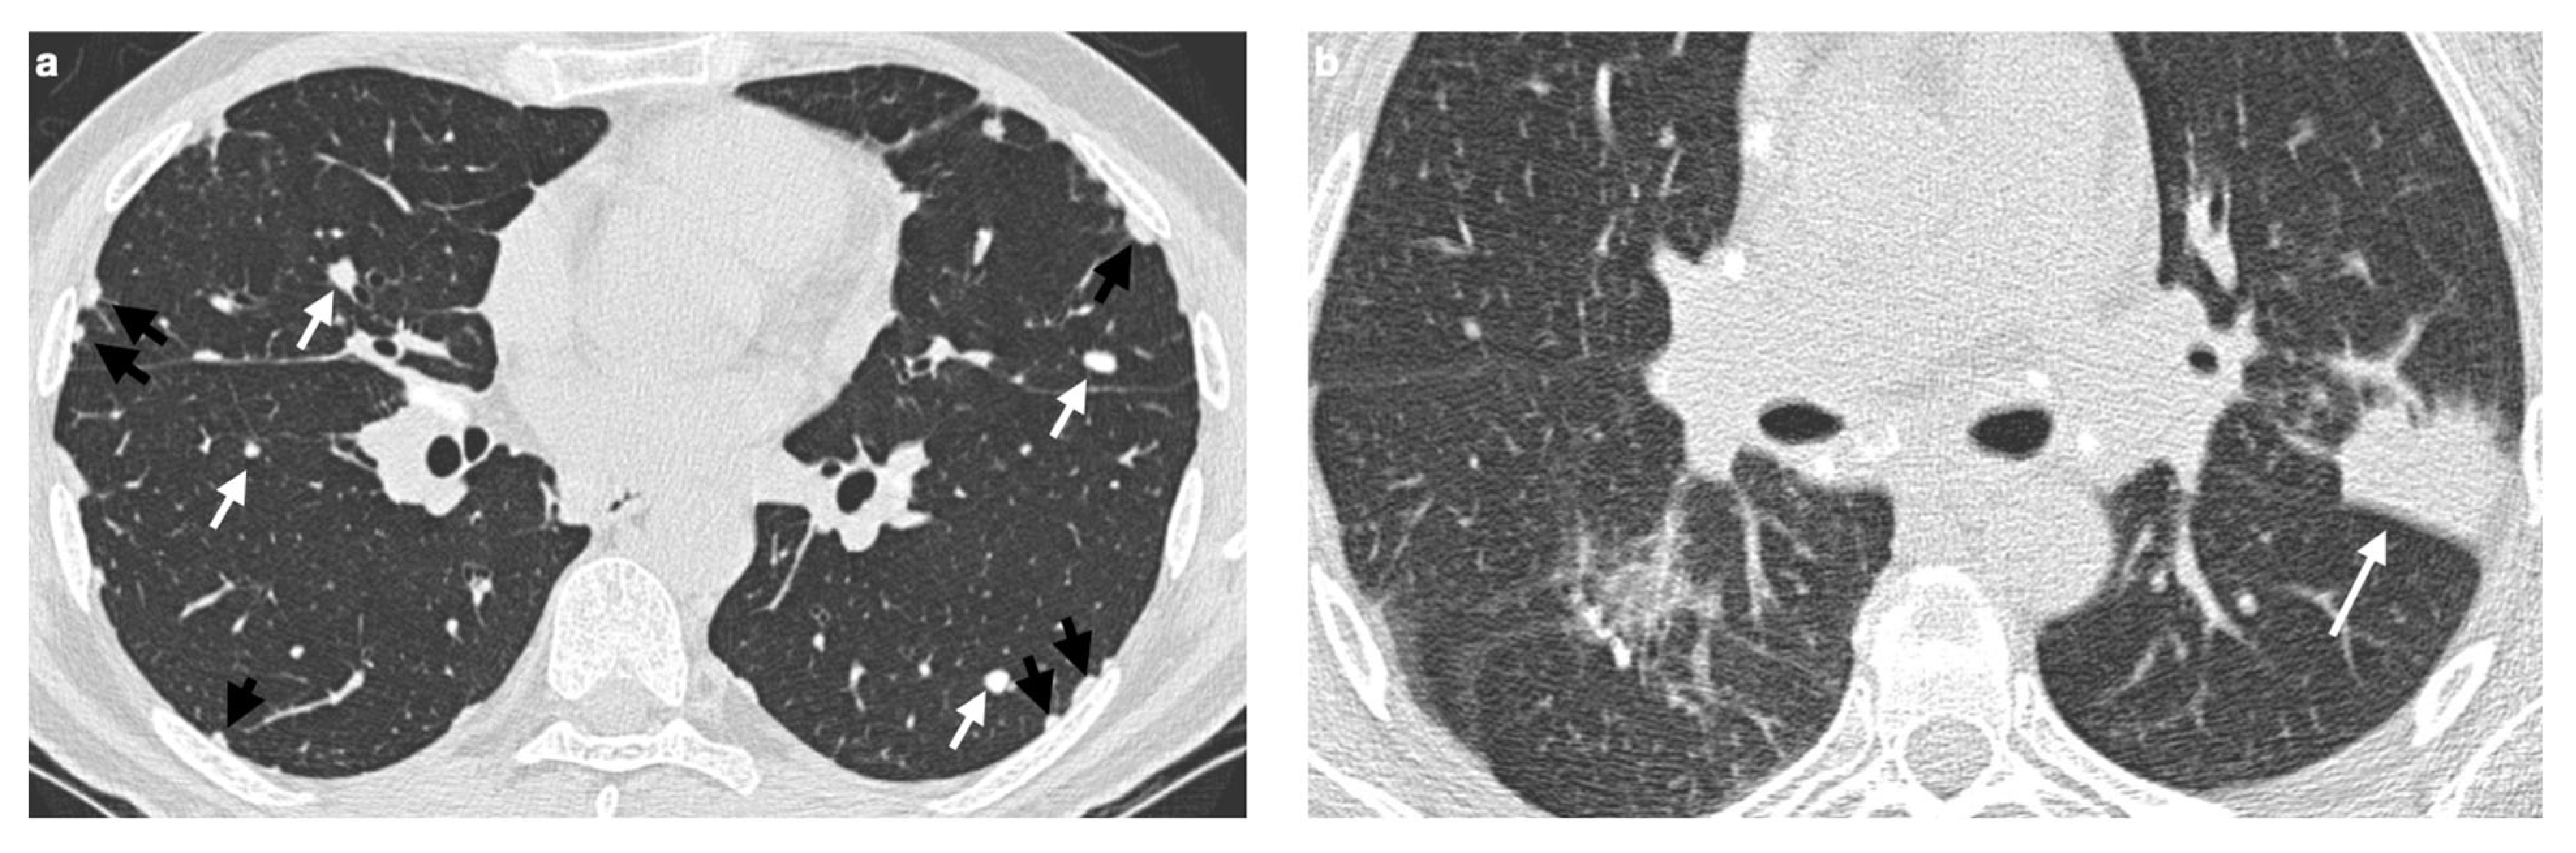

4. Pulmonary Interstitium

4.1. Typical Imaging

4.2. Atypical Imaging

4.2.1. Nodules and Masses

| Distribution | Perilympathic (75–90% of cases); bilateral and symmetric involvement, especially in the middle and upper lobes |

| Nodule size | Micronodules 2–4 mm in diameter |

| Morphology | Nodules with well-defined margins, round shape |

| HRCT localization | Peribronchovascular interstitium, interlobar fissures, interlobular septa |

| Evolution | Possible coalescence of micronodules into macronodules over time |